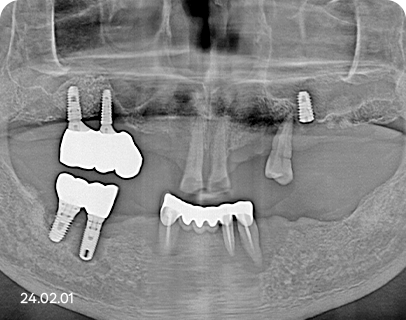

NO, 저희는 꼭 필요한 자리에만 심습니다.

임플란트는 많이 심을수록 튼튼한 건 맞습니다.

하지만, 잇몸 상태 그리고

치료 비용의 부담을 고려하여

세종스타치과는 꼭 필요한 자리에만

심어드리고 있습니다.

전체 임플란트 식립 예시